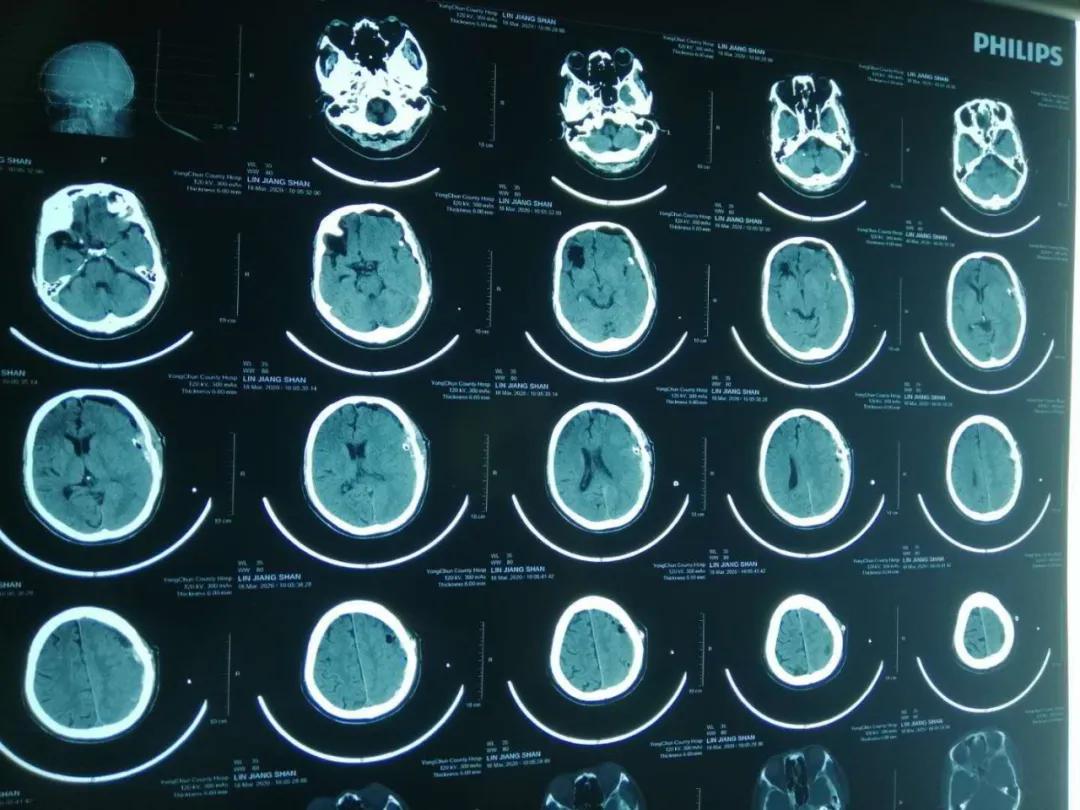

患者林某,男性,82岁,反复头晕半个月,症状时好时坏,未引起重视,未进行治疗,4月27日突发右侧肢体无力,无不能言语,无人事不省,无口吐白沫、双眼上吊、四肢抽搐,无大、小便*禁失**。经查,该患者左侧额、颞、顶部亚急性硬膜下血肿,右侧顶部硬膜下少量出血未除。左侧额颞顶部硬膜下血肿清除术后,于2020.04.28在全身麻醉下行“内镜下颅内血肿清除术+脑积液漏修补术+颅骨修补术”。

术后降低颅内压及抗感染治疗,患者状态良好,病情得到恢复。

术前

术后